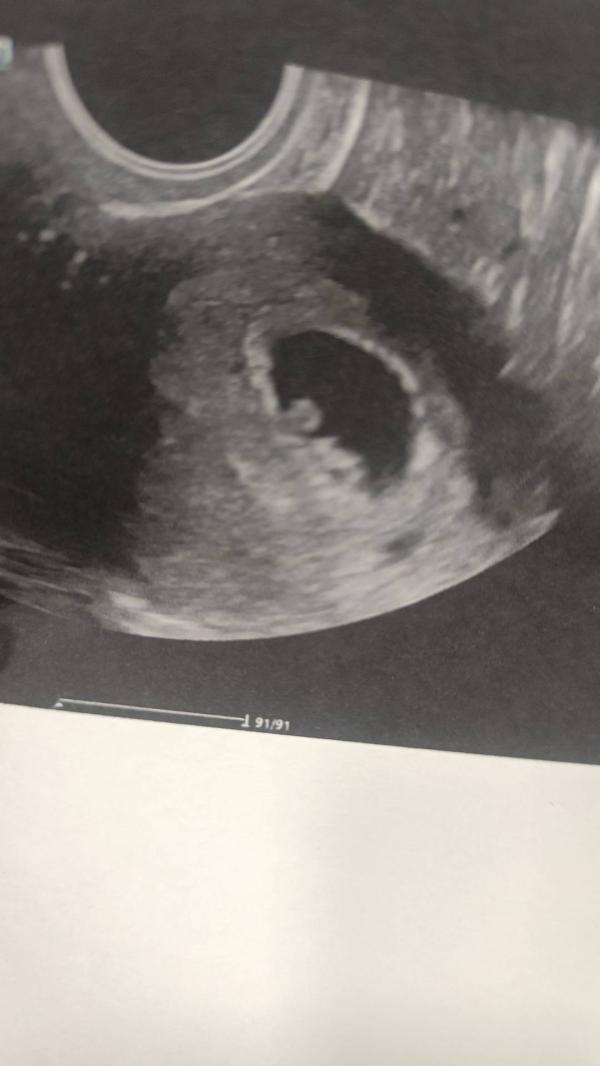

Что значит, если малыш лежит на спине на УЗИ при беременности

Сходили послушали сердцебиение

Все хорошо

Микро малыш просто лежит на спине 🫨

6 недель 4 дня